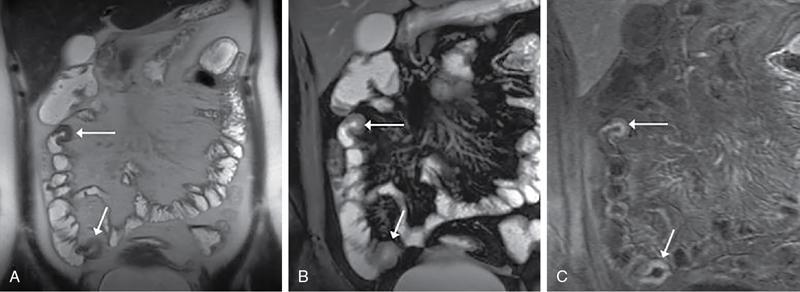

Kavita Saggar, Archana Ahluwalia, Devinder Pal Singh Dhanota, Geetika Khanna, Chander Gupta Inflammatory bowel disease (IBD) represents chronic idiopathic inflammation of the gastrointestinal [GI] tract. The common subtypes are Crohn’s disease, ulcerative colitis (UC) and indeterminate colitis (Fig. 7.11.1). Approximately 20%–25% of patients present in childhood or adolescence. Of these, nearly two-thirds of cases are caused by Crohn’s disease with an incidence of 4.56 per 1000,000 children (Fig. 7.11.2). IBD can affect any portion of the GI tract; however, children have a much higher incidence of small bowel and colonic involvement (Table 7.11.1). Currently, there is no single diagnostic test for the evaluation of IBD. Diagnosis is based on a combination of history, physical examination, serum inflammatory markers, endoscopy, histopathology and imaging. A host of imaging modalities is available for the evaluation of IBD in children. Traditionally, barium fluoroscopic studies, namely small bowel follow-through or small bowel enteroclysis (SBE) were used. However, barium studies depict only the mucosal abnormalities and do not evaluate the extraluminal extent of disease. Ultrasonography (US) is increasingly being used in the workup of patients with IBD. Small intestine contrast ultrasound (SICUS) and contrast-enhanced ultrasound (CEUS) are used for evaluation of IBD. CEUS requires intravenous administration of microbubble contrast such as Sonovue, and SICUS requires small bowel adequate luminal distension with ingestion of an iso-osmolar contrast agent such as polyethylene glycol. A recent meta-analysis of 33 studies showed that CEUS had better accuracy than US, CT and MR for the detection of inflammation and differentiation of fibrotic and inflammatory strictures. However, the extent of the disease was better evaluated by CT and MR. Currently, computed tomography enterography (CTE) and magnetic resonance enterography (MRE) have emerged as the most effective tools for imaging small bowel in patients with IBD. CTE and MRE can accurately depict the spectrum of imaging findings related to severity, extent and complications of IBD and thereby help in guiding management and assess the response to treatment. MRE is an attractive imaging modality due to lack of ionizing radiation, inherent multiplanar capability and excellent soft tissue contrast resolution. In addition, dynamic/cine imaging allows assessment of peristalsis and accurate identification of the diseased segment. The major disadvantage of MRE is high cost, lower spatial and temporal resolution and long examination time. Crohn’s disease is a transmural granulomatous disease that can affect any part of the GI tract from the oral cavity to anus, often involving multiple discontinuous segments of bowel. Patients have a genetic predilection to develop an abnormal immunologic response to environmental factors including food and gut flora, leading to a chronic inflammatory response. Small bowel is the major site of involvement. Terminal ileum is the most common location which is involved in approximately one-third patients. The colon is affected in 50% patients. In 15%–20% cases, there may be isolated involvement of the colon without affecting the small bowel. The clinical importance of small bowel Crohn’s disease is the impact that a diffuse small bowel disease is expected to have on child’s growth and development. Thus, objective evaluation of small bowel is essential in differentiating from other enteropathies and in directing the management of patients with IBD. Two methods used for imaging small bowel with barium using fluoroscopy are standard small bowel follow through (SBFT) and SBE. Small bowel evaluation with barium has long been considered the most common, noninvasive, inexpensive and easily accessible radiological method, but it has been replaced by cross-sectional imaging. In the current scenario, the only indication of barium studies is when CTE or MRE cannot be done because of nonavailability or are not feasible. Ultrasound is being increasingly used to assess the activity of Crohn’s disease, especially in paediatric patients. Greyscale ultrasound allows morphologic assessment of bowel wall and mesentery. Normal small bowel loops are easily compressible with the transducer and the wall thickness is <2 mm. The bowel loops show regular peristalsis and are mobile. Colour Doppler shows minimal intramural or perienteric vascularity. The salient sonographic features of Crohn’s disease are: There is marked concentric or eccentric bowel wall thickening [>2.5–3 mm]. The mural echogenicity depends upon the degree of inflammation and fibrosis. In the acute phase, mural stratification is maintained (Fig. 7.11.3A and B). In patients with long-standing disease, a target or pseudo-kidney appearance may be seen. In long-standing burnt-out disease, there is submucosal fat deposition. The actively inflamed bowel segments show increased vascularity on Doppler ultrasound (Fig. 7.11.4A and B). CEUS with microbubbles can objectively assess the disease activity. A stricture is seen as a segment of bowel wall thickening with apposition of the luminal surfaces. There is persistent luminal narrowing with variable degree of upstream dilatation and hyperperistalsis. Doppler imaging reveals hyperemia in strictures with an active inflammatory component. Fibrotic strictures do not demonstrate increased blood flow. A major advantage of ultrasound is real-time imaging which allows the evaluation of bowel peristalsis. The diseased segments of the bowel (inflamed or fibrotic) show reduced peristalsis and often appear fixed in position. Mesenteric inflammation is commonly seen in active Crohn’s disease. Sonography reveals thickening of mesentery with heterogeneous echogenicity due to oedema. Doppler ultrasound shows increased vascularity due to engorgement of vasa recta. Fibrofatty proliferation of mesentery seen in chronic disease appears as abnormally thickened echogenic fat that displaces the bowel loops. Reactive mesenteric lymph nodes (up to 1.5 cm) can be seen in the active inflammatory phase of Crohn’s disease. These appear as hypoechoic round or oval structures with preserved fatty hilum. Sinus tracts and fistula often arise from or just proximal to a strictured segment and appear as linear areas of altered hypoechogenicity extending from serosal surface of gut. There may be tethering and/or angulation of the affected bowel segment. Abscesses are discrete well-defined fluid collections with internal debris, septation or nondependent echogenic gas. Colour Doppler reveals peripheral hyperemia with absent blood flow centrally. Ultrasound may be falsely negative if an abscess contains a large amount of air and can be mistaken for an air-filled bowel loop. Both CTE and MRE identify the transmural, extramural and mesenteric manifestations of small bowel Crohn’s disease. The imaging findings can be categorized as: Asymmetric long segment (>3 cm) bowel wall thickening is a consistent feature of Crohn’s disease. The mesenteric border is usually more severely affected. It is imperative that the bowel should be distended when assessing bowel wall thickening. Thickening may be mild (3–4 mm), moderate (5–10 mm) or severe (>10 mm) (Fig. 7.11.5A and B). This is the most consistent finding in the active inflammatory stage, defined as increased signal intensity or attenuation on contrast-enhanced scans in a noncontracted segment of bowel in comparison with adjacent small bowel segments. Hyperenhancement may be stratified into bilaminar and trilaminar patterns. In the bilaminar pattern, there is hyperenhancement of only the inner wall (often referred to as mucosal hyperenhancement), and in the trilaminar pattern, there is inner and outer wall hyperenhancement, with the submucosal oedema giving a halo effect. Hyperenhancement may also be homogeneously transmural or patchy. A potential pitfall in contrast enhancement is that normal jejunal loops enhance more than ileal loops and collapsed bowel segments can show apparent hyperenhancement (Figs. 7.11.6A,B and 7.11.7A–C). These are defined as multifocal (>3) segmental areas of involvement with normal intervening gut loops. This is an important feature that differentiates Crohn’s disease from UC when colon is predominantly involved (Figs. 7.11.5A,B and 7.11.7A–C). This is identified as an increased signal of the thickened bowel wall on T2W images. The inflamed walls also show restricted diffusion. The hyperintense signal due to intramural oedema persists on T2W fat-saturated images differentiating it from intramural fat seen in long-standing burnt-out disease (Fig. 7.11.8A and B; refer Fig. 7.11.20A–D).